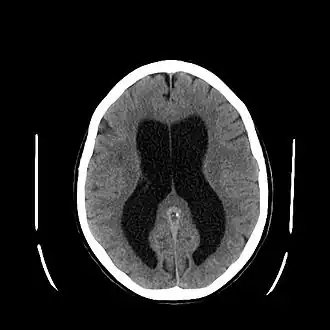

![]() Hematoma subdural (flecha), sangrado entre la duramadre de las meninges y el cerebro, se produce con frecuencia en SBS | ||

El síndrome del niño sacudido, también conocido como síndrome del niño zarandeado o agitado o síndrome del bebé sacudido (SBS) es una constelación de hallazgos médicos (a menudo designada como la "tríada"): hematoma subdural, hemorragia retinal, y edema cerebral, por la que los facultativos, de acuerdo con los conocimientos médicos actuales, deducen maltrato infantil causado por sacudidas violentas, sacudidas muy peligrosas debido a que el cerebro del bebé o niño pequeño aún no ocupa toda la caja craneal. En la mayoría de los casos no hay signos visibles de lesión externa. El síndrome del niño sacudido es un subconjunto de una forma de maltrato infantil más amplia llamada trauma cerebral abusivo o trauma cerebral por maltrato.[1] El CDC, Centers for Disease Control and Prevention, de los Estados Unidos, identifica SBS como "una lesión en el cráneo o contenidos intracraneales de un bebé o niño pequeño (< 5 años de edad) debido a un impacto contundente y/o sacudida violenta".[2]

Lesiones características asociadas con SBS incluyen hemorragia retinal, fracturas múltiples de los huesos largos, y hematomas subdurales (hemorragia cerebral).[8] Estas señales se han desarrollado con los años como las señales aceptadas y reconocidas de maltrato infantil y síndrome del bebé sacudido. Los profesionales médicos sospechan firmemente de sacudida como causa de lesiones cuando el bebé o niño pequeño presenta hemorragia retinal, fracturas, lesiones de tejidos blandos o hematoma subdural, que no pueden ser explicados por trauma accidental u otras afecciones médicas.[9]

El SBS puede ser mal diagnosticado o subdiagnosticado, y los cuidadores pueden mentir o no ser conscientes de los mecanismos de la lesión.[18] Normalmente, no hay signos visibles de la afección.[18] El examen de un oftalmólogo a menudo resulta fundamental en el diagnóstico de síndrome de bebé sacudido, ya que formas particulares de derrame ocular son muy características.[33] Imágenes por resonancia magnética también pueden mostrar sangrado retinal;[17] Puntualmente esto puede resultar útil si un examen del oftalmológo se retrasa o no está disponible.[cita requerida] Afecciones que deben ser descartadas incluyen hidrocefalia, síndrome de muerte súbita del lactante (SMLS), trastorno convulsivo, y enfermedades infecciosas o congénitas como meningitis y trastornos metabólicos.[19][34] Se utilizan exploración por TAC e imágenes por resonancia magnética para diagnosticar la afección.[18] Afecciones que pueden acompañar SBS incluyen fracturas óseas, lesión de la vértebras cervicales (en el cuello), hemorragia retinal, hemorragia cerebral o atrofia, hidrocefalia, y papiledema (hinchazón del disco óptico).[14]